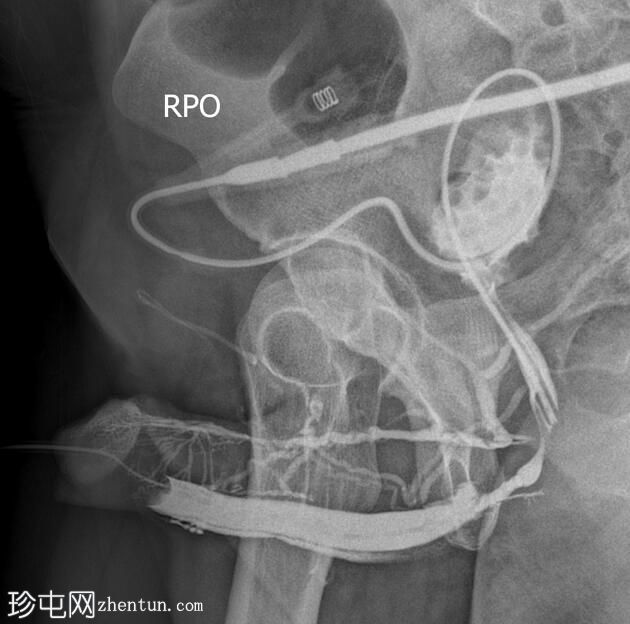

冠状位

斜位

逆行尿道造影显示球部近端尿道存在长段狭窄,造影剂广泛渗入阴茎静脉丛和盆腔静脉。

阴茎尿道外观正常。

造影剂已开始充盈膀胱。

该患者尿流细弱,表现为球部尿道长段狭窄。造影剂渗入与注射时施加的压力有关。